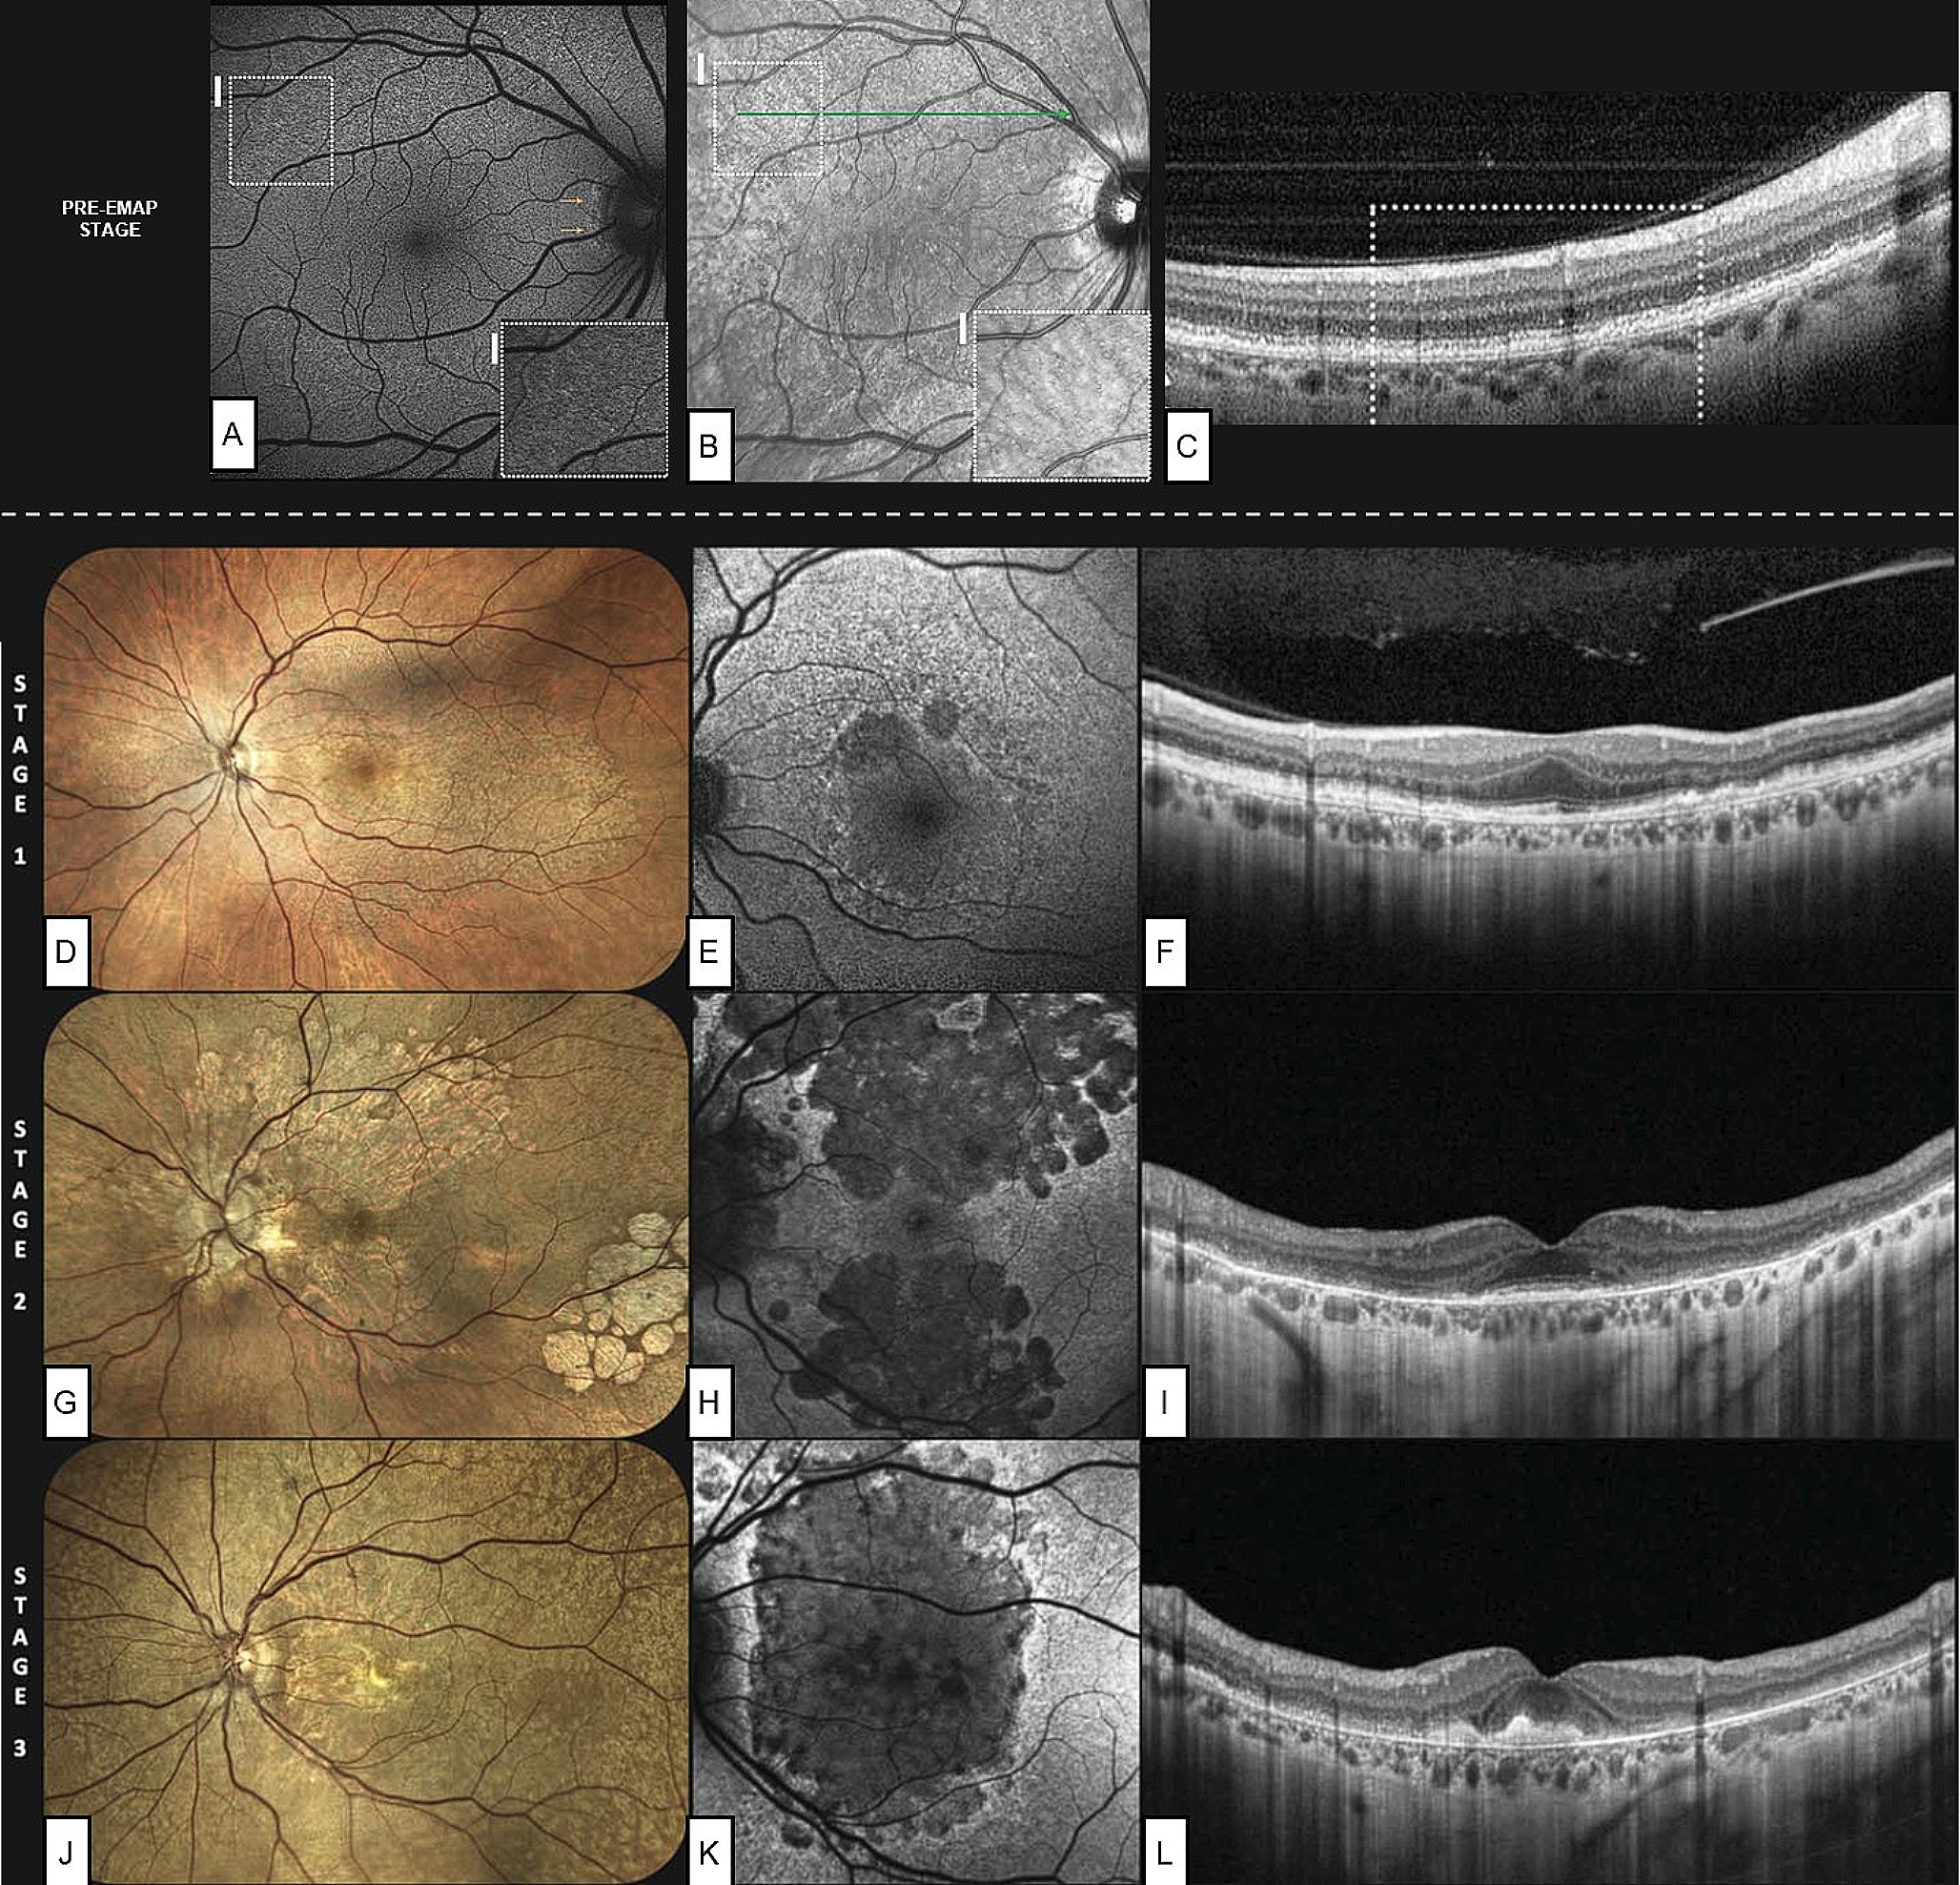

EMAP stages

A recent research proposed a three-stage EMAP categorization scheme, based on multimodal imaging results and visual symptoms [20] (Table 1). Moreover, a recent report distinguished EMAP pattern based on topographic involvement: predominantly central, predominantly peripheral and mixed forms [30].

Stage 1 is characterized by the splitting of RPE–BrM and scattered RPDs extending into the retinal midperiphery, with non-confluent patches of RPE atrophy limited to the superior macula. In this stage, a good preservation of visual acuity is maintained. In Stage 2, RPE atrophy appears confluent and widespread, acquiring a prominent vertical direction, but the fovea is still preserved. Though visual acuity stays comparatively high, visual symptoms such as reading difficulties and poor dark adaption become more noticeable. In Stage 3, the illness affects the fovea, with a consequent significant decline in visual acuity. Moreover, foveal involvement may result from either RPE atrophy (stage 3 A) or subretinal fibrosis development (stage 3B) [20] (Fig. 3).

Fig. 3

Staging system proposed by Romano et al., with the addition of the pre-extensive macular atrophy with pseudodrusen (pre-EMAP) stage, proposed by Fragiotta et al. Mild autofluorescence (A) and infrared (B) alterations are visible in the superior perifovea, corresponding to RPE granularity (C) and initial splitting of the retinal pigmented epithelium-basal lamina-Bruch’s membrane (RPE-BL-BrM) complex. Fundus photographies (D, G, J), fundus autofluorescence (E, H, K) and optical coherence tomography scans passing through the fovea (F, I, L), show the progressive atrophy involving the posterior pole and assuming a vertically-oriented shape.

Courtesy of Fragiotta et al. [15] and Romano et al. [20]